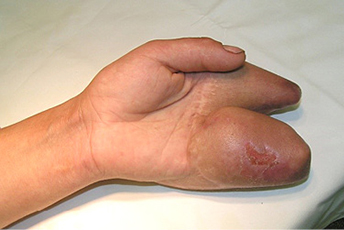

13 pav.

14 pav.

15 pav.

Atokieji rezultatai, praėjus maždaug 13 m. po rekonstrukcinių operacijų. Pacientės taip pat paprašyta parodyti, kaip sugeba suimti rašiklį. Nufotografuota donorinė dešinės pėdos vieta (13–15 pav.)